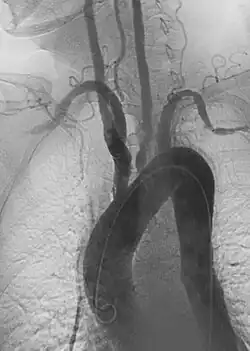

• Endovascular aneurysm repair: Placement of endovascular stent-graft across an aneurysm to prevent expansion or progression of the defective vessel.[6]

Aneurysm refers to pathologic dilation of an artery to greater than 1.5 times its normal size. True vascular aneurysms are due to degenerative processes in the wall of the artery. Aneurysms can be solitary or multiple and are sometimes found in association with various clinical syndromes, including forms of vasculitis or connective tissue diseases. Aneurysms are typically classified by major shapes, either fusiform (tubular) or saccular (eccentric). Ectasia is another broad term for an enlarged vessel, but is not necessarily pathological. Rupture is a dreaded complication of aneurysms that can lead to extensive, difficult to control bleeding. Aneurysms can also clot, or thrombose, and rapidly occlude the involved vessel, leading to acute distal ischemia.

1. Aortic aneurysms include thoracic, abdominal and thoracoabdominal aneurysms. Treatment strategies are customized depending on the location, size, rate of growth and extent of the aneurysm as well as the medical comorbidities of the patient. For example, an intact, small but slowly growing aneurysm may be safely monitored with serial imaging for months or years before elective repair is considered. Elective endovascular aortic grafting is now routinely attempted when possible. Endovascular aortic repair (EVAR) refers to treatment of an abdominal aortic aneurysm, while thoracic endovascular aortic repair (TEVAR) is performed on the thoracic aorta. A ruptured aneurysm may be taken emergently for open, endovascular or combination repair.

A variety of endovascular grafts are available, and each has advantages and disadvantages depending on the characteristics of the aneurysm and patient.[90]